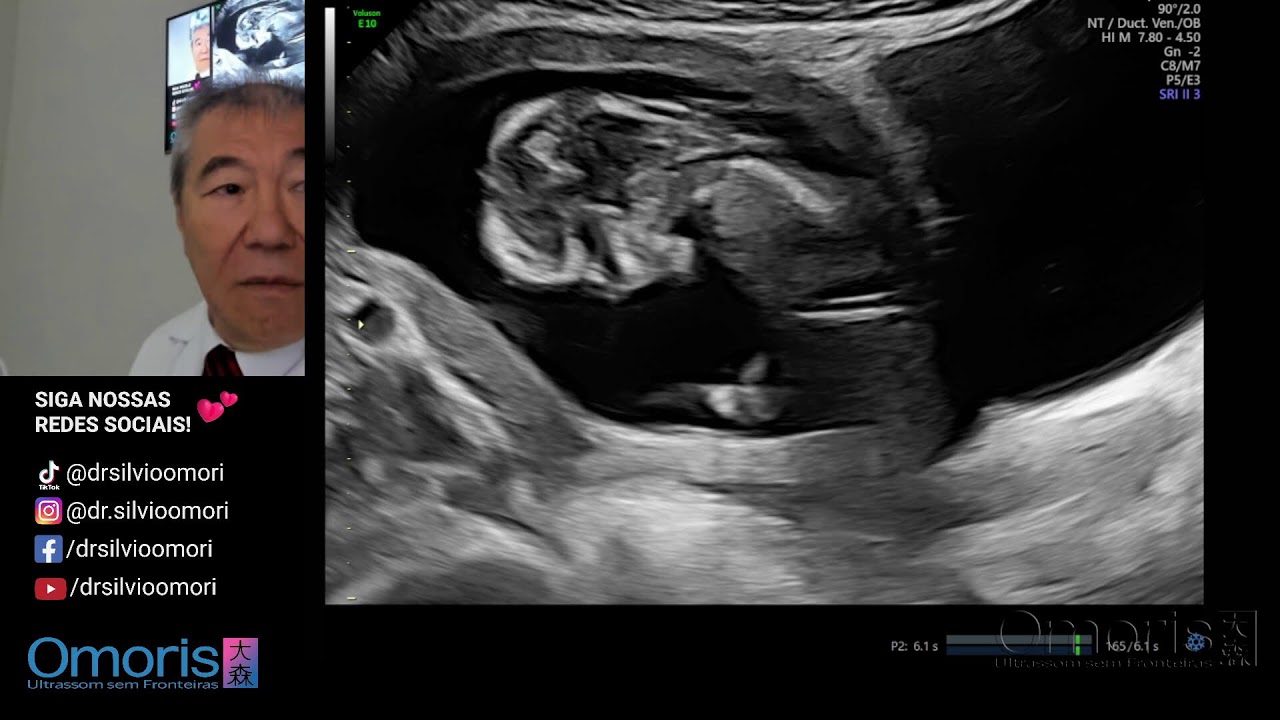

3D Gravidez 27 semanas.

Описание: 3D Gravidez 27 semanas.

O Método Omoris possibilita o desenho do contorno do feto em imagens de ultrassom, permitindo uma melhor visualização no útero da mamãe.

Com mais de 40 anos de experiência, o Dr. Silvio Omori e médico especialista em ultrassonografia gestacional.